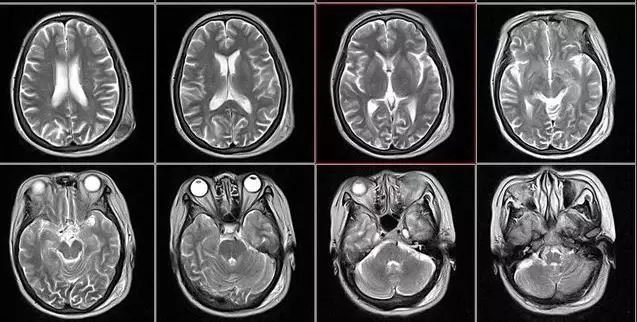

2、颈椎腰椎——最佳选核磁、次选CT

0.webp (4).jpg

颈椎病、腰椎间盘突出等椎间盘疾病需要观察椎间盘与相应的神经根,要想更好观察这些软组织,最优选择就是核磁。同样,对于关节、肌肉、脂肪组织检查,核磁也是首选。